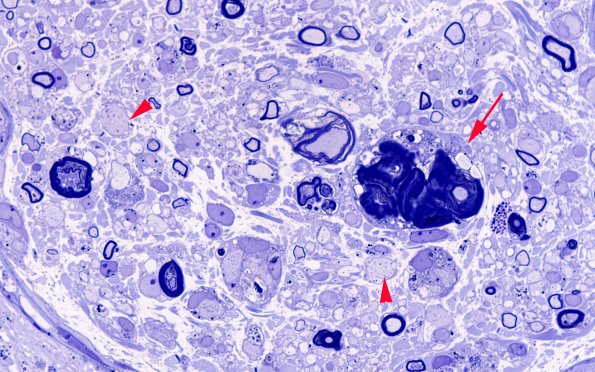

This fascicle is particularly rich in demyelinated axons (arrowheads, 2A6). The structure marked with an arrow is somewhat puzzling appearing to contain a large amount of debris enclosed by macrophages or a multinucleated giant cell. (plastic section)

(plastic section)